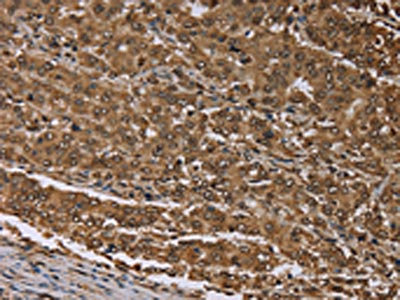

The image on the left is immunohistochemistry of paraffin-embedded Human liver cancer tissue using CSB-PA912611(MEIS1 Antibody) at dilution 1/30, on the right is treated with synthetic peptide. (Original magnification: ×200)

The image on the left is immunohistochemistry of paraffin-embedded Human thyroid cancer tissue using CSB-PA912611(MEIS1 Antibody) at dilution 1/30, on the right is treated with synthetic peptide. (Original magnification: ×200)